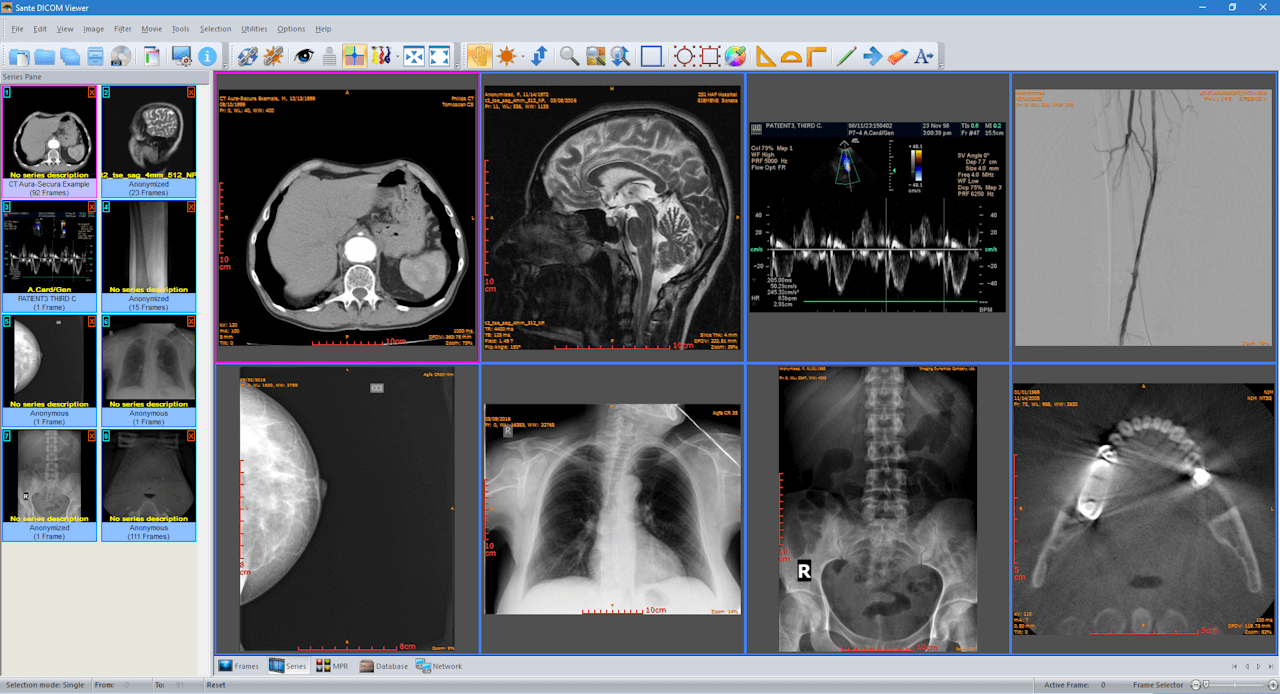

It is a robust application that is easy to use too. While it does not offer cloud storage, it can function as a mini-PACS server. It has the capacity to batch-anonymize and batch-convert to image formats. The free version is valid for 45 days only, after which a lifetime license can be purchased at a reasonable cost.

| 12. | Sante | Windows | Mini-PACS available | Y | N | N | Picture, movie and data files | 100 MB | Intel Core i3/ 2 GB RAM; Screen resolution 1064x768, true color | Free for 45 days only |